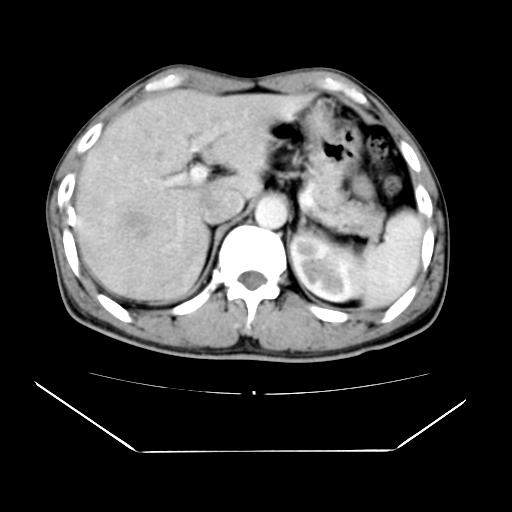

男性,55岁,外院体检afp明显升高,但b超未发现异常,否认乙肝病史。来我院ct增强。有延时扫描。

延时扫描完全充填,血管瘤

肝脏右叶动脉期可见低密度影,至延迟期被充填,考虑血管瘤可能性大。

肝右叶病灶

不排除肝右叶肝癌可能。

这个不是肝右静脉吗,这么大的病灶b超不可能发现不了吧

如果这个是癌灶的话则下腔静脉有瘤栓可能

肝6段血管瘤

血管瘤可能性大。

是肝右静脉吧

考虑肝右静脉影。